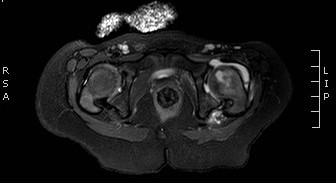

39.a.

Image

39.b.

39. a-b.MRI, T2 weighted and T1 weighted, postcontrast axial images. Signal intensity increase and increased contrast enhancement in the bone marrow of the left femoral neck,. 2 years old child, osteomyelitis. (with the courtesy of dr. Gábor Rudas).